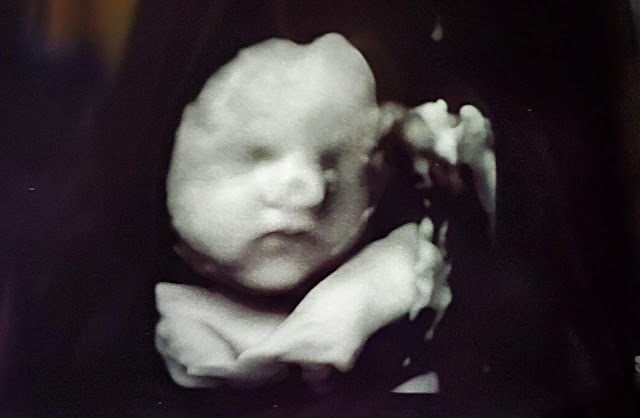

| Meet the newest member of the extended Milligan clan. Sargie's son, Shea, and Nikki, are expecting our newest granddaughter later this summer. |

Yes, indeed, a baby girl will be coming our way sooner rather than later. Shea and Nikki live in Oconto, Wisconsin, about an hour and a half away and we're excited for the little one to arrive. This will bring our total grandbaby count to eleven.